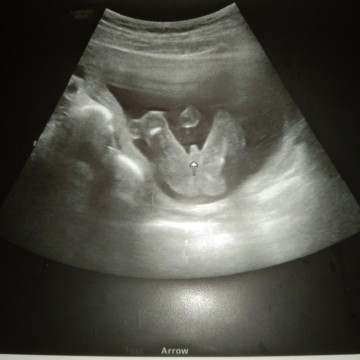

17+5 มีแต่คนทักจะได้ลูกสาว

แม่ไม่ต้องลุ้นแล้ว อ้าโชว์ฉ่ำๆไปเลยจ้า ไหนใครบอกว่าแม่จะได้ลูกสาว #ดิ้นเก่งมากๆค้าบ #แม่ๆรู้เพศน้องกันกี่วีคค่ะ

ส่วนอันนี้แม่ๆดูออกมั้ยค่ะว่าชายหรือหญิง ถ้าชายทำไมมันไม่จู๋แหลมเหมือนแม่ๆเลย

ชายใช่มั้ยค่ะแม่ อยากได้ชายญ2แล้ว